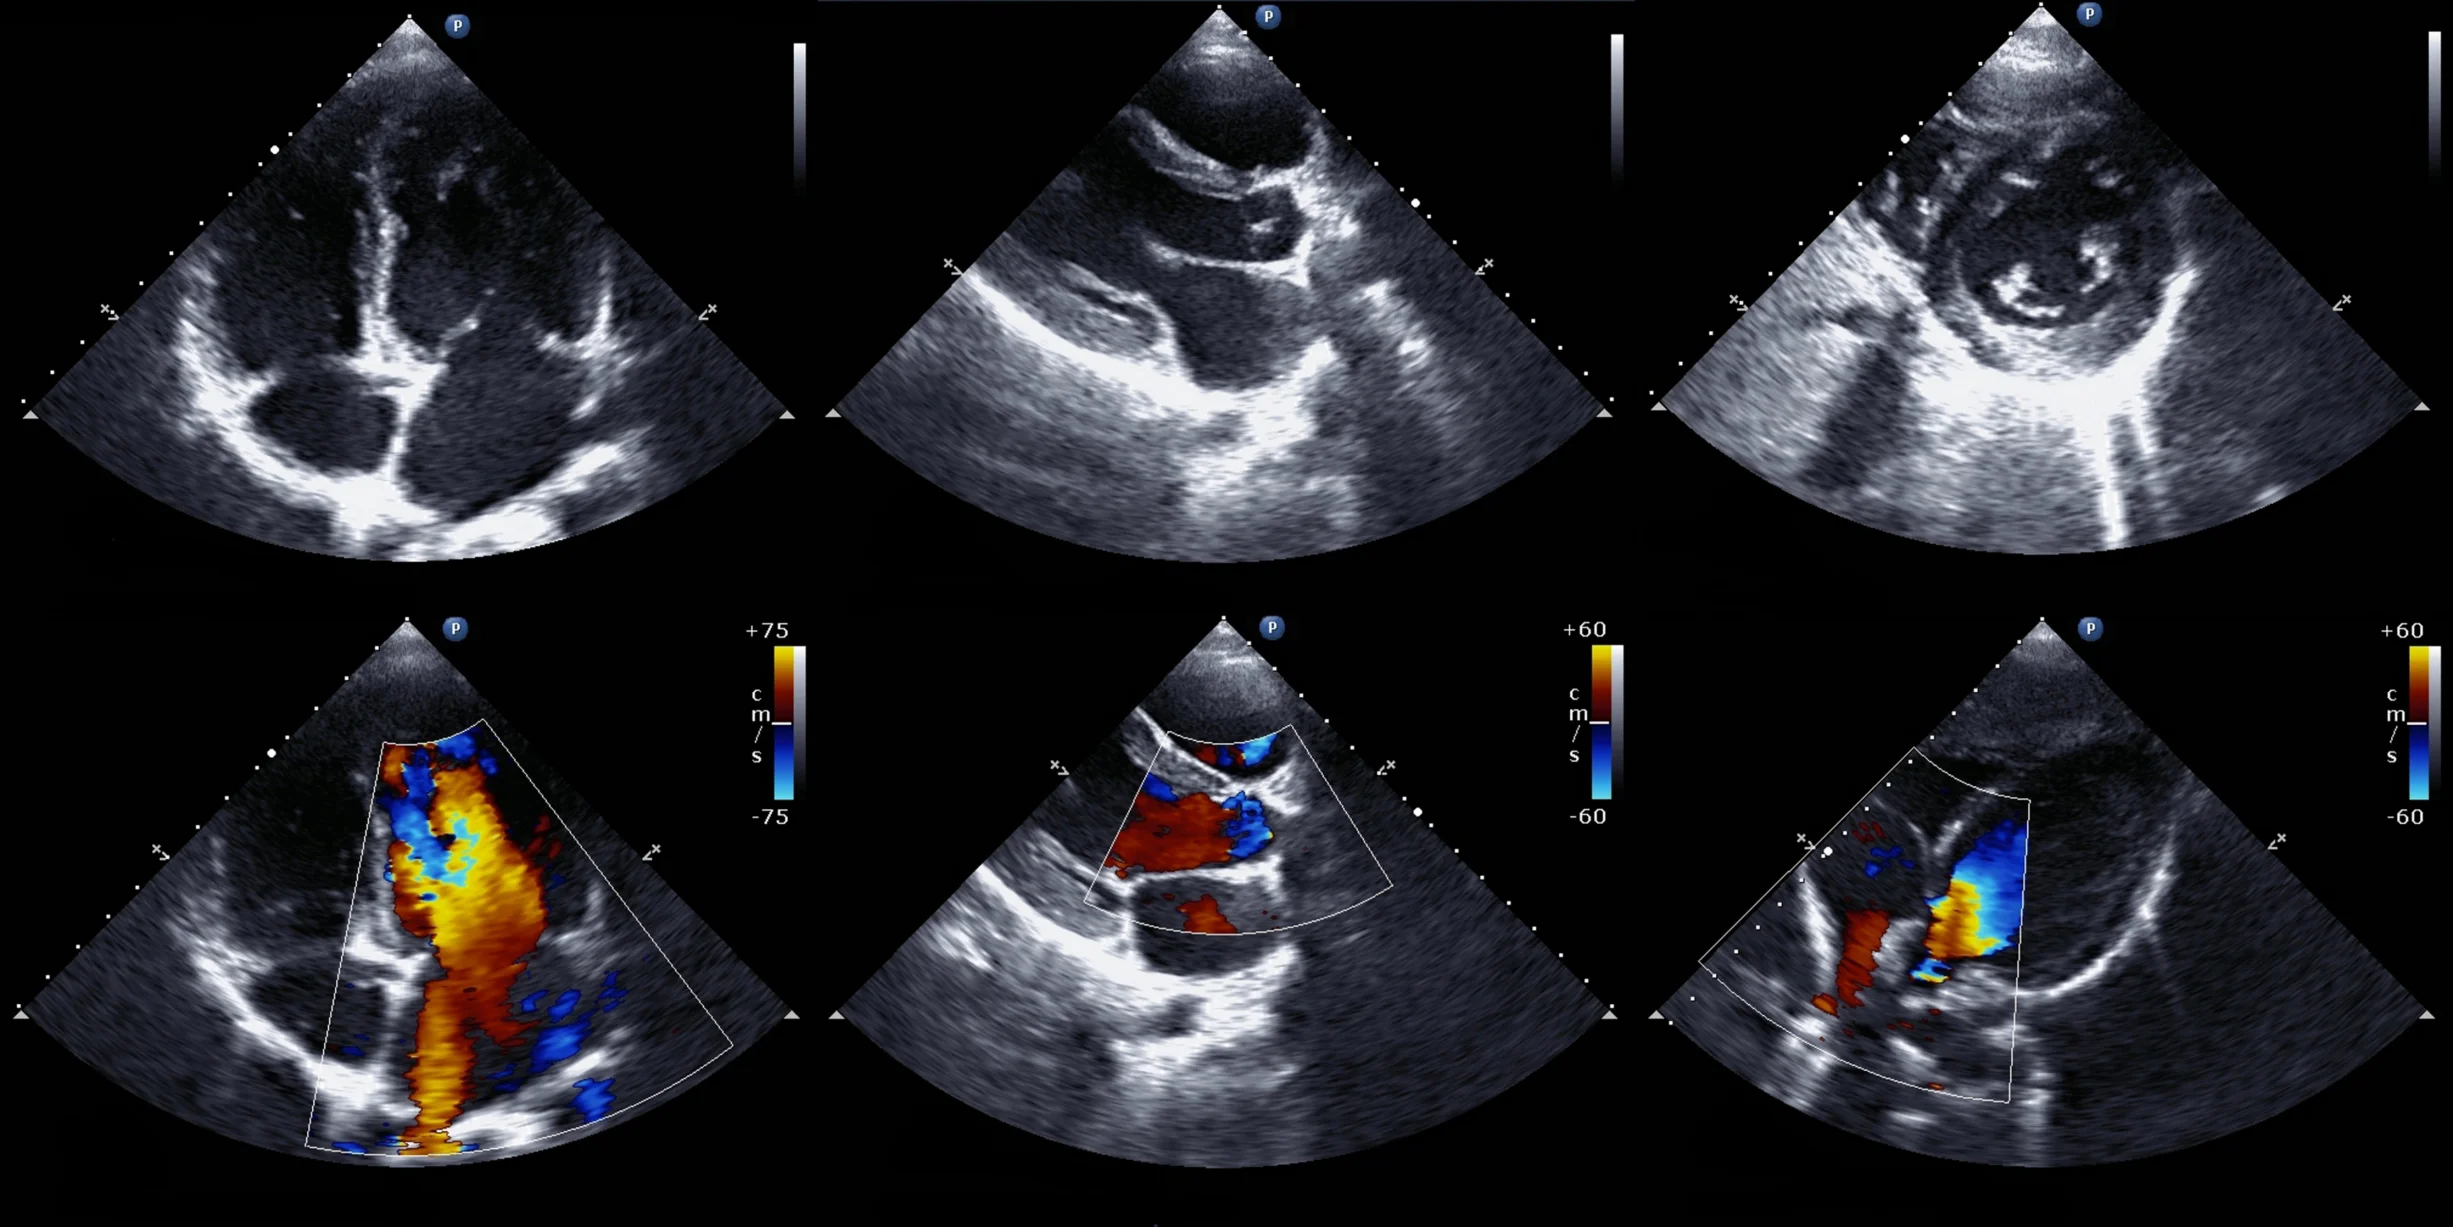

echocardiography

Precise Diagnostics offers services in Adult Transthoracic Echocardiography, Adult Congenital Transthoracic Echocardiography, Exercise Stress Echocardiography and Dobutamine Stress Echocardiography including contrast imaging, 3D and global longitudinal strain.